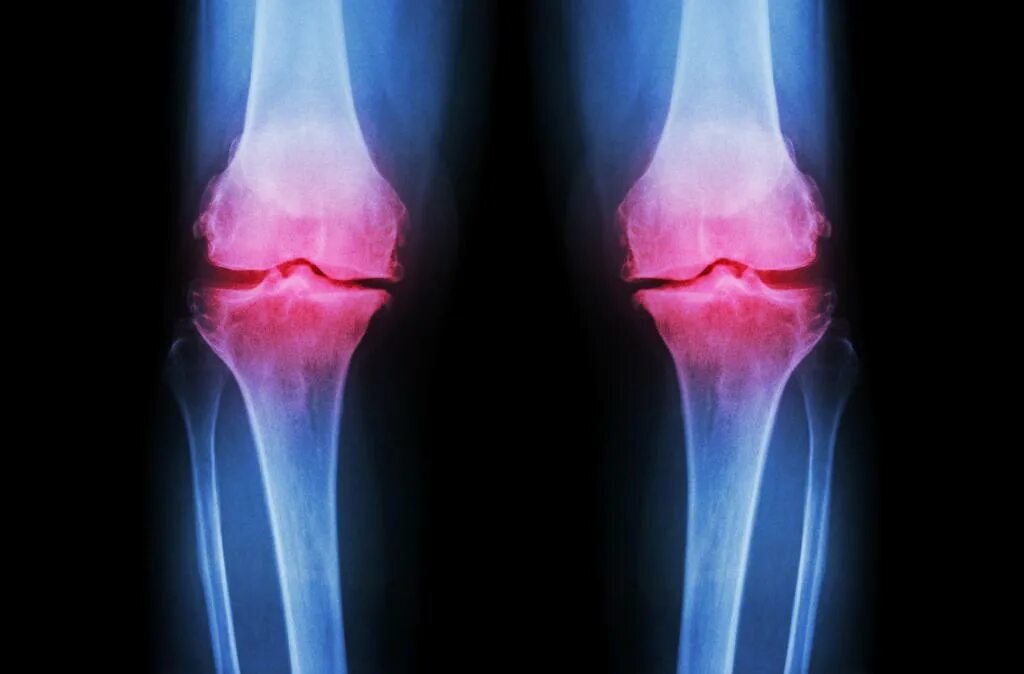

Гонартроз коленного сустава какой врач